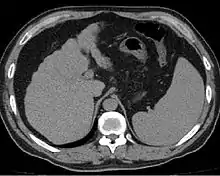

Cross-section of human liver with cirrhosis

Liver cirrhosis on CT imaging of the abdomen in transverse view